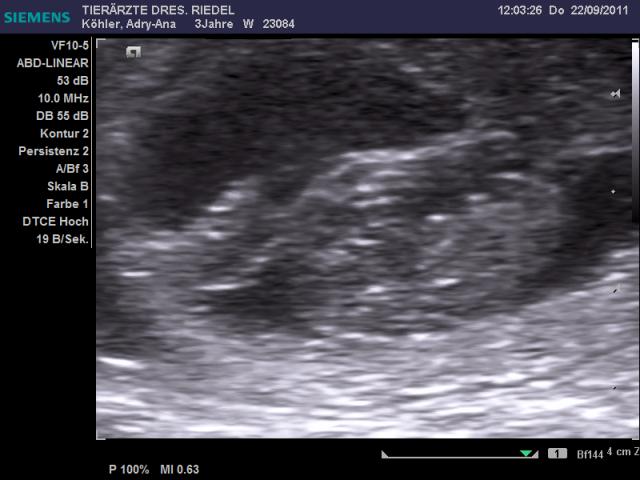

Adry-Ana-Fly wurde am 25./26.08.2011 vom Champion-Rüden Earl Grey Designed by Blue DeLux alias >>Robbi<< gedeckt. Die Verpaarung war erfolgreich und Adry-Ana-Fly hat am 25. 10. 2011 hübsche Welpenbabys auf die Welt gebracht. Fotos folgen in Kürze. Video von Adry & Robbi

Hier die ersten Bilder der Ultraschalluntersuchung: